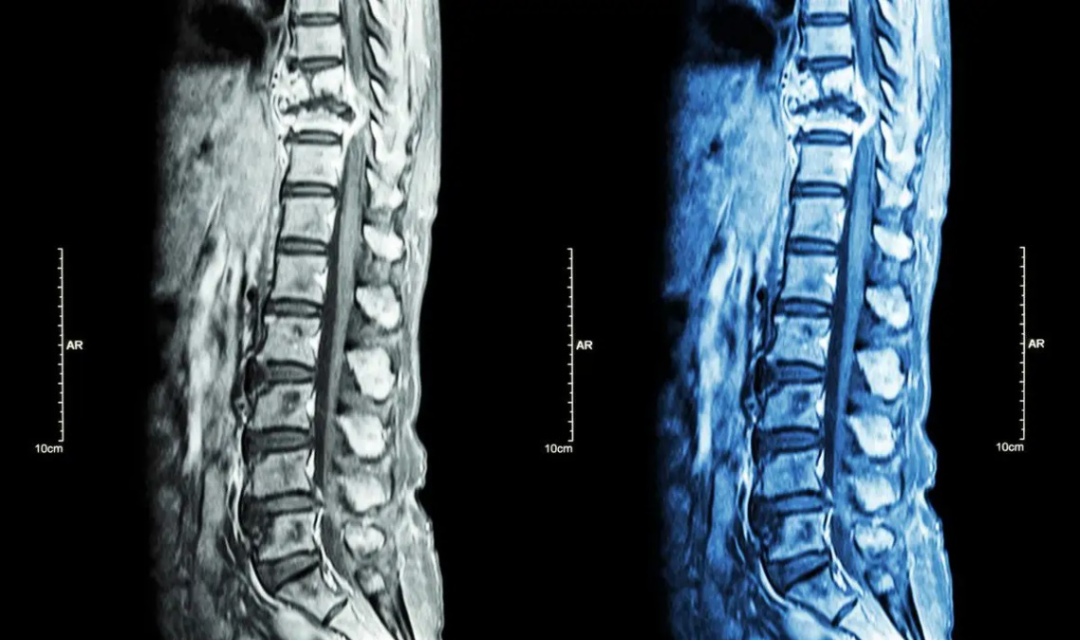

骨关节炎是一种关节退变性疾病,其特征表现为关节软骨完整性被破坏。关节炎可影响某个关节的所有部分,引起肌肉疼痛、炎症或行动不便,常伴有骨质增生。由于OA发病因素的多样性,其潜在的病理生理学和疾病的演变可能有很大不同。年龄、体重指数和性别是引起OA发生的最直接因素,另外过度的机体负荷、强烈的体育活动以及营养供应不足被认为是关节软骨退变的重要原因。

目前临床上OA的治疗方法主要包括使用止痛药、非甾体抗炎药、关节腔注射润滑补充剂,以及在骨关节炎晚期运用关节置换外科手术等方法。然而这些方法只能减轻骨关节炎病人的疼痛和暂缓OA进程,并不能逆转因关节软骨不可逆退变而引起的OA病程。